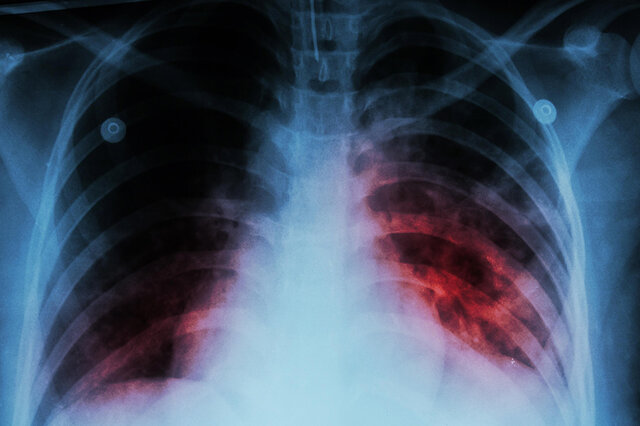

ویدیو/ افزایش ابتلا به سل بعد از کرونا؛ کودکان در خطرند

موارد ابتلا به سل، کشندهترین بیماری عفونی جهان در میان کودکان اروپا و آسیای مرکزی نسبت به سال گذشته نزدیک به ۱۰ درصد افزایش یافته است. طبق گزارش مرکز اروپایی پیشگیری و کنترل بیماریها (ECDC)، متعلق به سال ۲۰۲۳، منطقه اروپا همچنان درگیر پیامدهای همهگیری کرونا است.